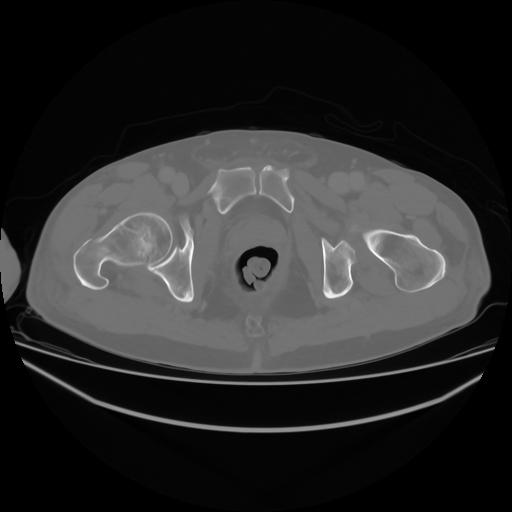

4 CUERPO,CE,Axial,3.0,CUERPO,,